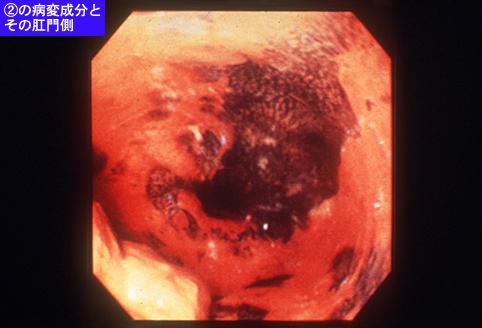

A case of carcinosarcoma associated with broad superficial esophageal cancer.

Tokyo Pref., Cooperative study between National Cancer Center and Kyushu Cancer Center

[ Image ID:7502 ]

Location

Esophagus/More than one of the above

Technique, Method

Endoscopy

Macroscopic Types

Type 0/Others

Size

40 -

Depth of Tumor Invasion

submucosa